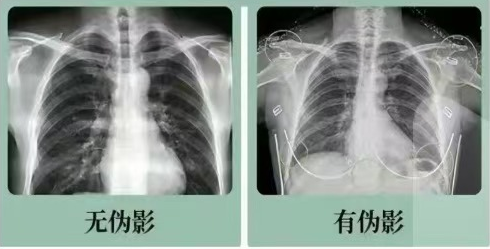

2.拍片为什么会要求脱衣服?

根据不同的检查部位,不同的检查方法,有着不同的图像要求。有时内衣、牛仔裤等衣物上的金属或衣服上装饰的小珠子不在检查范围内或不影响诊断的基础上,可以存在。但比如在拍摄到服上、衣服口袋里的金属或女性含有金属的内衣均会对诊断造成一定的影响,所以放射科技师会让您脱掉有影响的衣服。